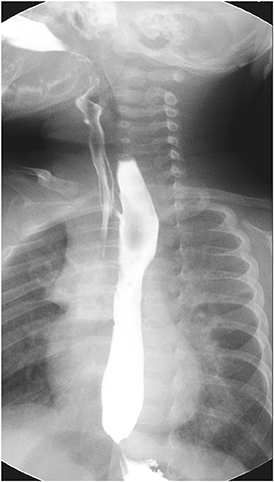

A male full-term neonate presented to emergency room with cyanosis after breastfeeding. The patient was delivered by planned caesarian section 12 hours before arrival. Chest radiograph taken on the first day of life was cleaned but the radiograph taken on the third day of life suggested aspiration pneumonitis (

Fig. 1). Upper gastrointestinal (GI) series showed gastroesophageal regurgitation with pulmonary aspiration but esophagoscopy and video esophagogram on the eleventh day of life showed no abnormality. Contrast esophagogram was followed on the 33

rd day of life, and an H-type TEF was found at 1 cm above the carina, at T4 level (

Fig. 2). Surgical repair was performed on the 37

th day of life through a right posterolateral thoracotomy incision. The fistula was positively identified, divided, and closed with non-absorbable interrupted sutures during the operation.

Fig. 1 Two days after birth (right), chest radiograph shows aspiration pneumonitis which was absent on the date of birth (left).

Fig. 2 H-type tracheoesophageal fistula at 1 cm above the carina (white arrows).